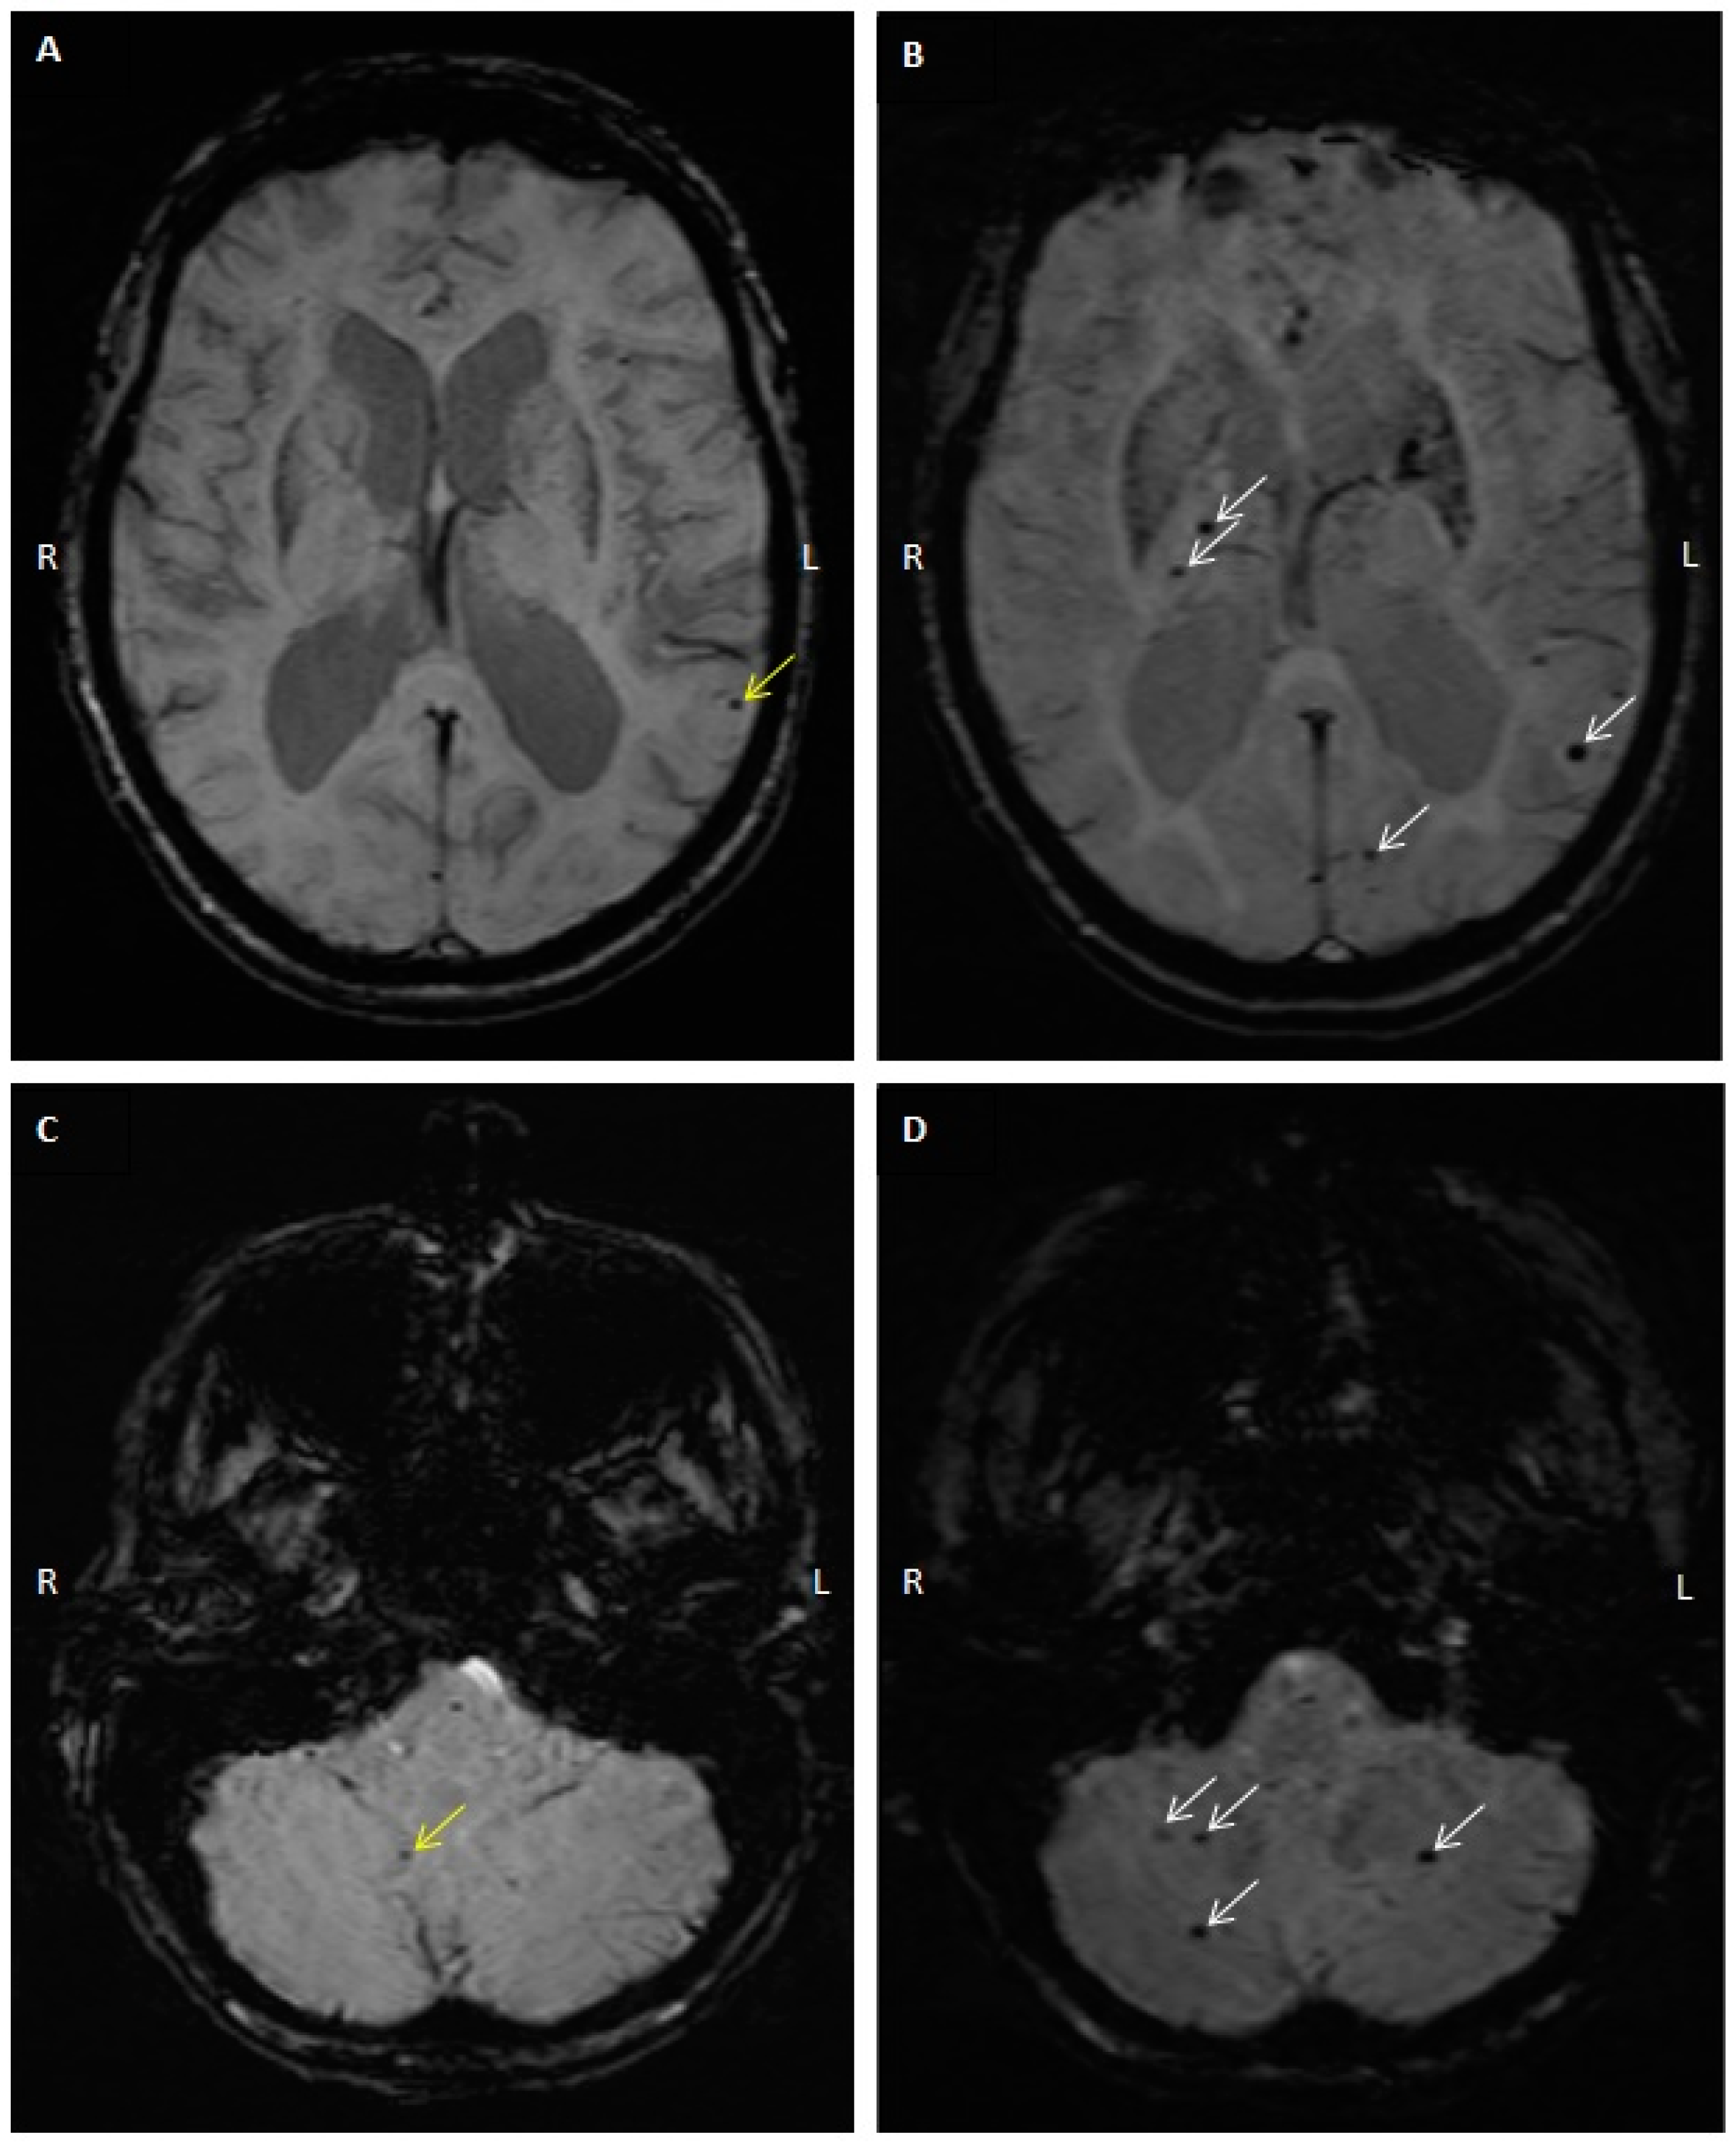

2.1. Patients

2.3. CMB Progression on Follow-Up MRI Studies

4.3. MRI and CMB Identification

4.4. Computed Tomography (CT) Interpretation and Cerebral Arterial Calcification Score